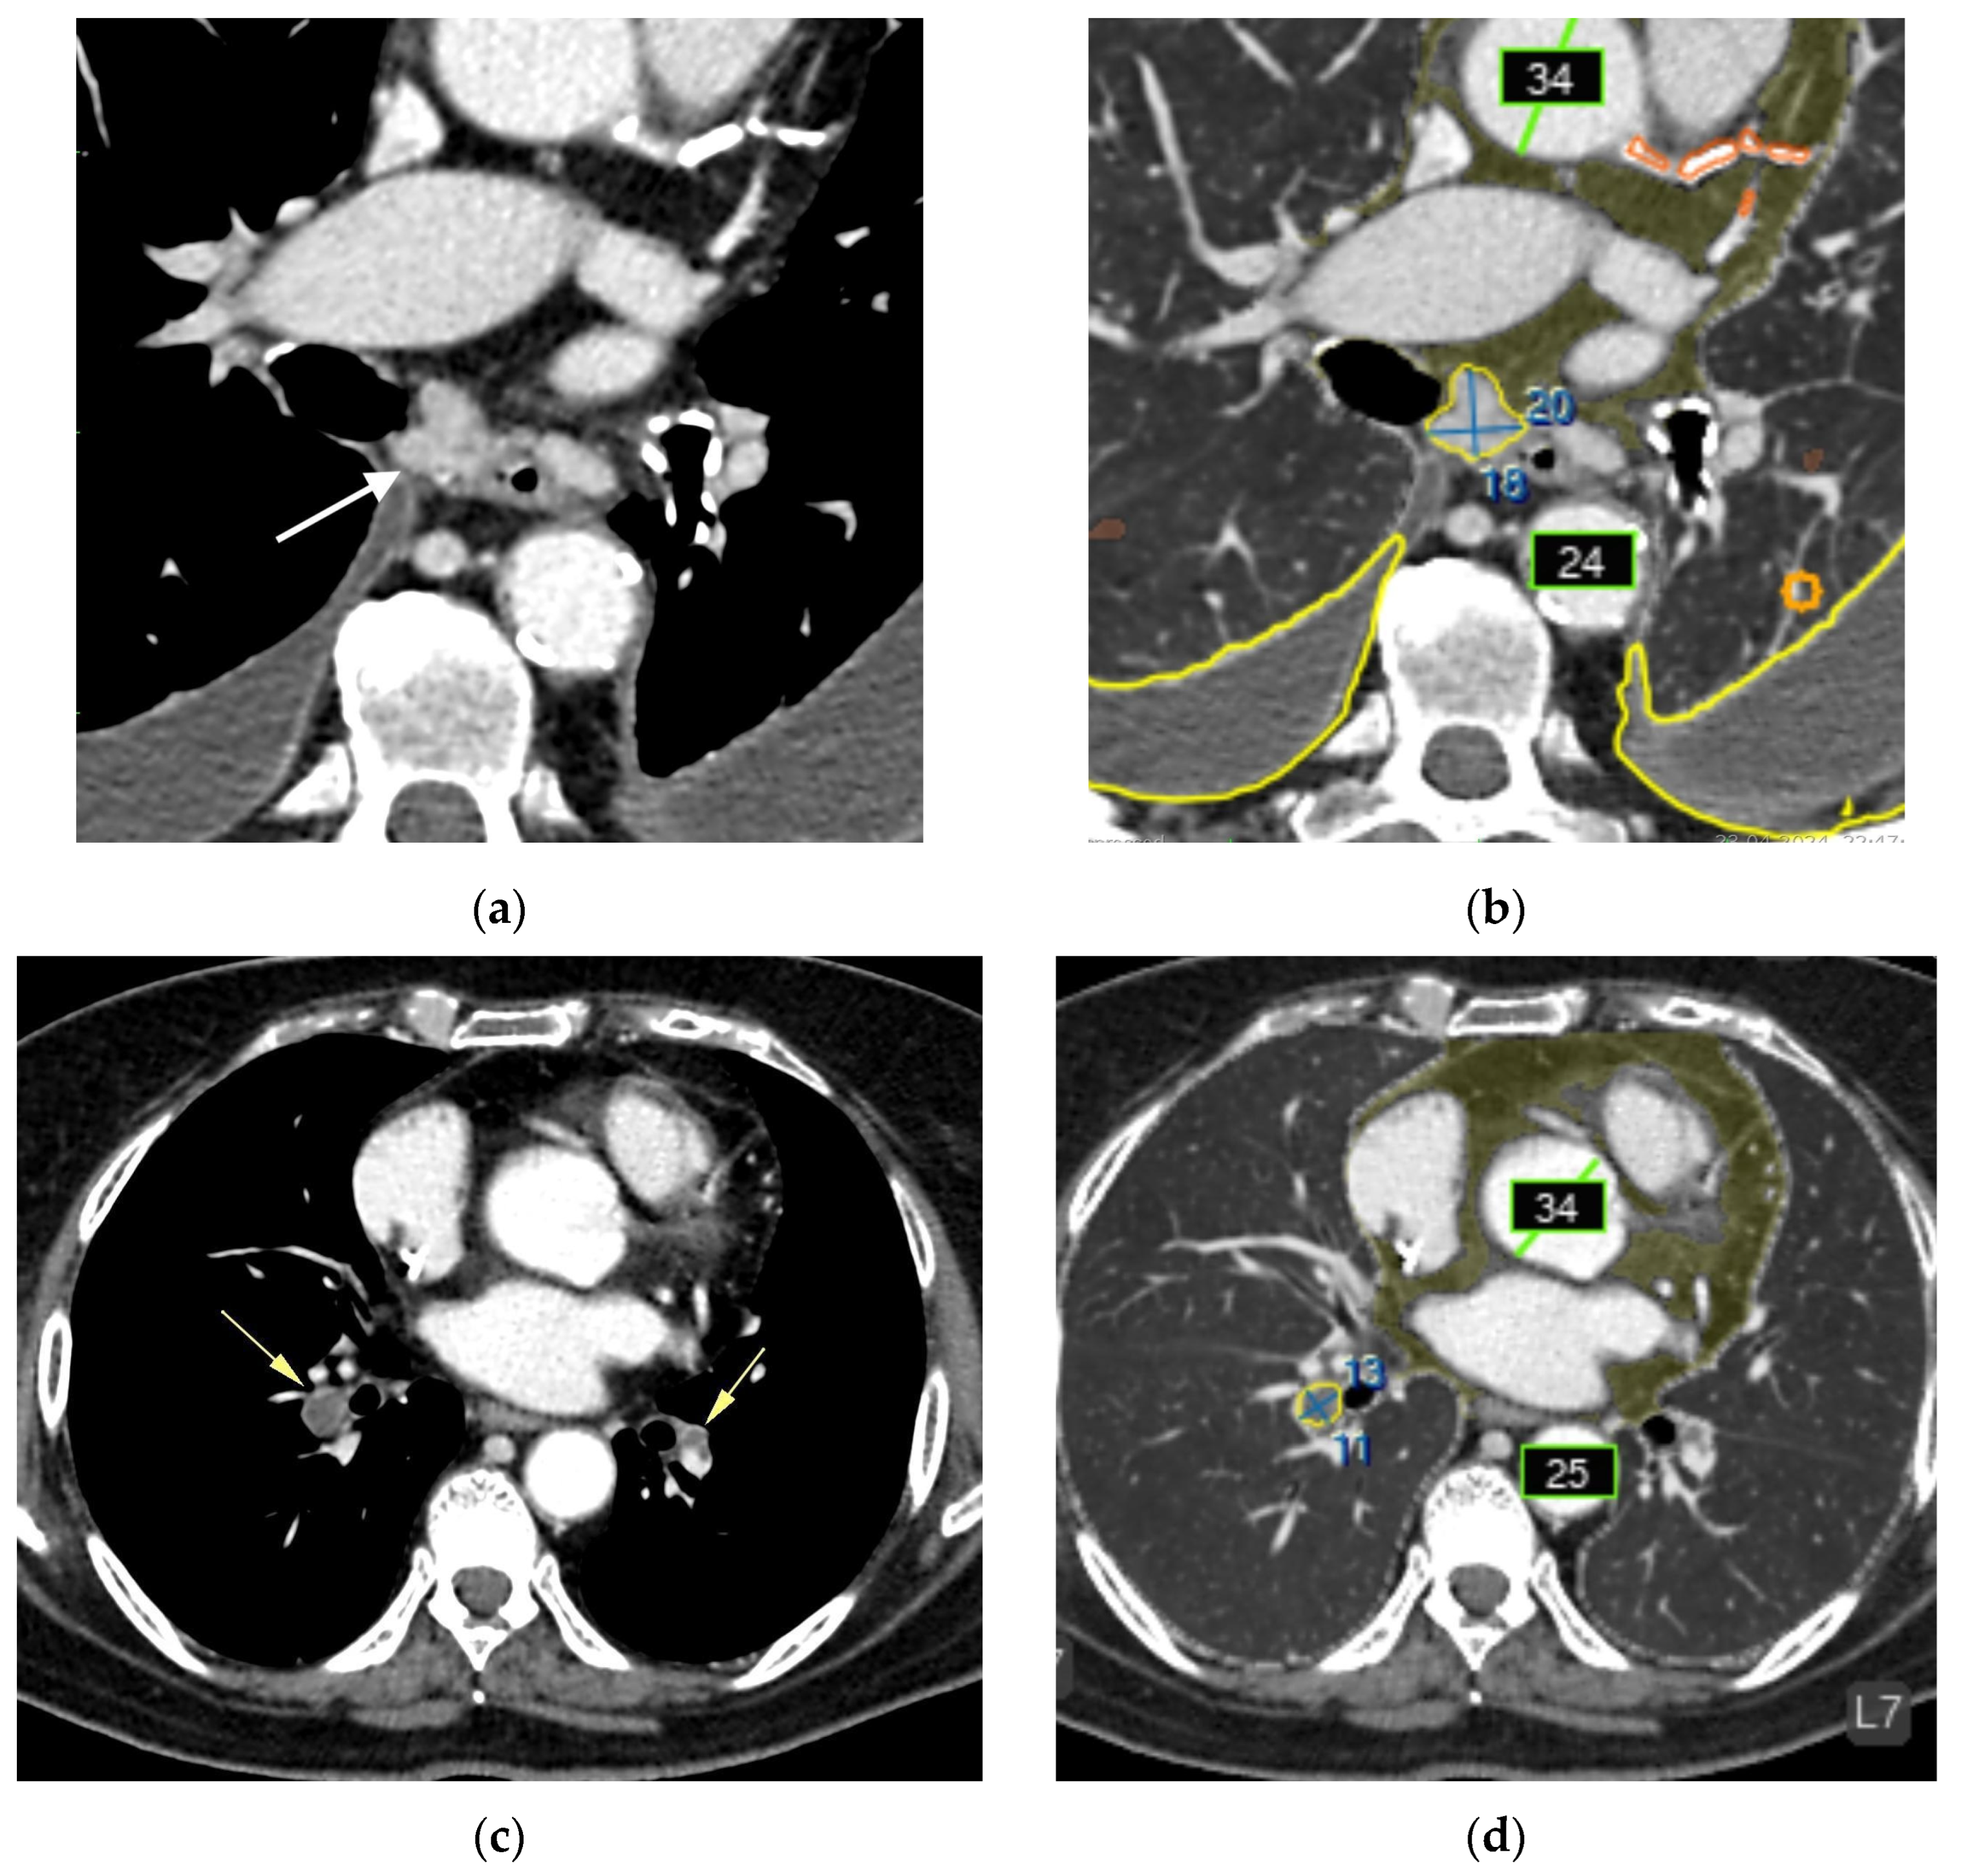

- Liver lesions (8);

- Renal lesions (2);

- Adrenal lesions (2);

- Impaired lung aeration (atelectasis, 2);

- Enlarged intrathoracic lymph nodes (3);

- Pulmonary nodule (1);

- Low vertebral body density (1);

- Urolithiasis (1) (Figure 4).